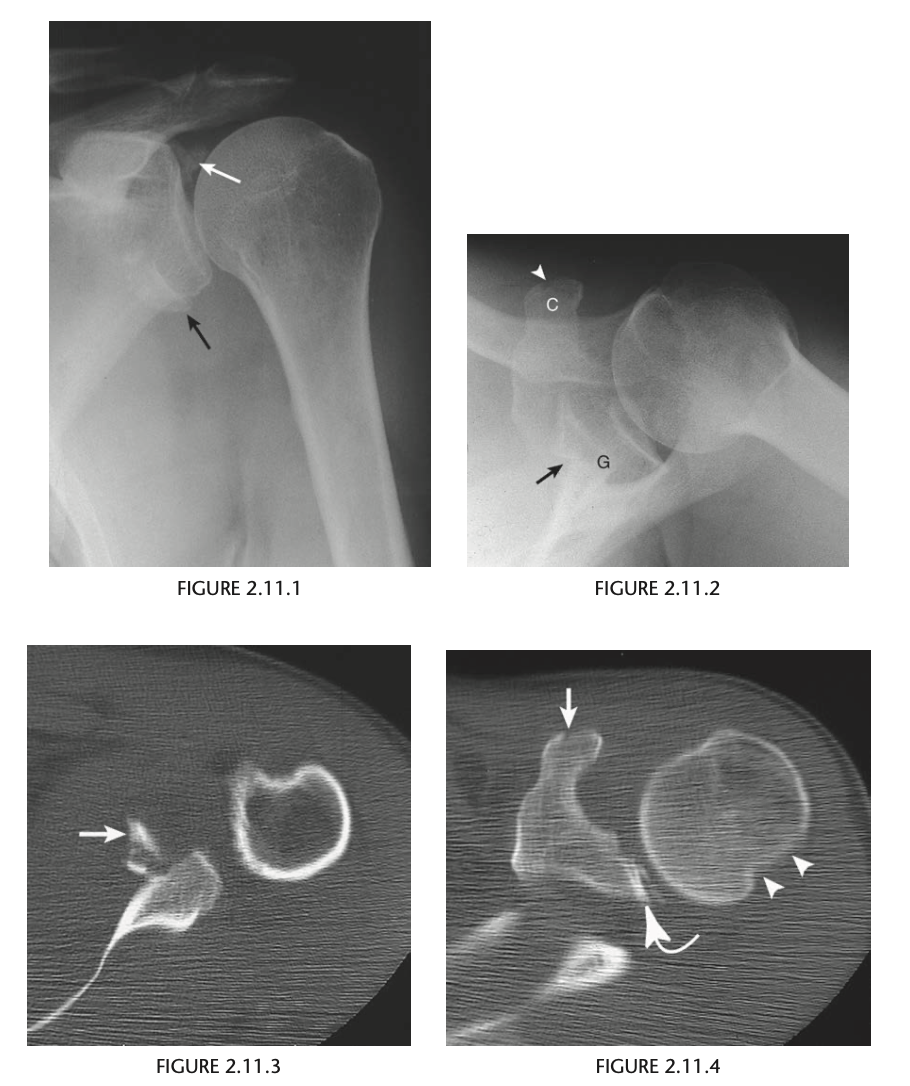

52 year old man with prior shoulder injury

Small fragments of bone (arrows) adjacent to the

superior and inferior aspect of the glenoid (G) and

a nondisplaced coracoid (C) fracture (arrowhead) - AP & Axillary view of left shoulder.

CT - fractures of the superior glenoid, coracoid process, and compression fracture of posterolateral aspect of humeral head (Hill Sachs)

Diagnosis: Bony Bankart lesion of the shoulder with

an associated Hill–Sachs deformity of the humeral

head caused by anterior glenohumeral dislocation

classic Bankart lesion is an avul-

sion of the anterior labroligamentous structures from

the anterior glenoid rim. A bony Bankart consists of

injury to the glenoid labrum and the anterior and in-

ferior rim of the glenoid.

Demonstration

of the fibrocartilaginous Bankart lesion requires CT

arthrography or MRI